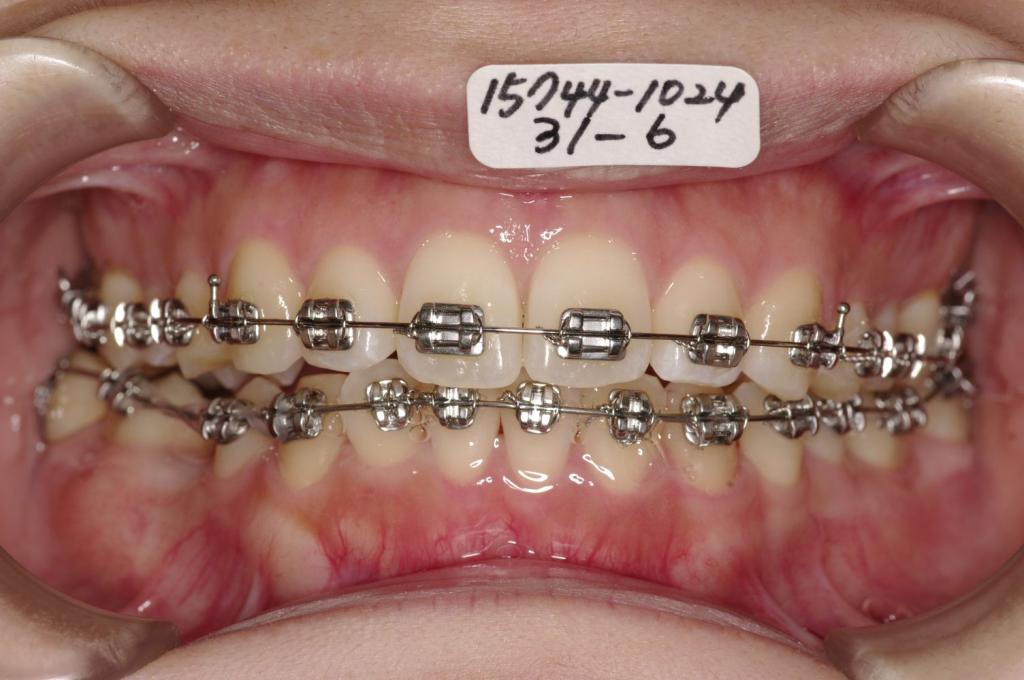

装置の種類及び治療法 診断:下顎右側第二小臼歯先天欠如 上下顎前突

治療方法および装置:マルチブラケット装置

High pull J-hook headgear

抜歯:非抜歯

抜歯:右上 /左上

右下E /左下8

欠損歯:右上8 /左上

右下5 /左下

治療期間:25ヶ月

装置写真

治療前

歯欠損の矯正治療前口内写真NO.146